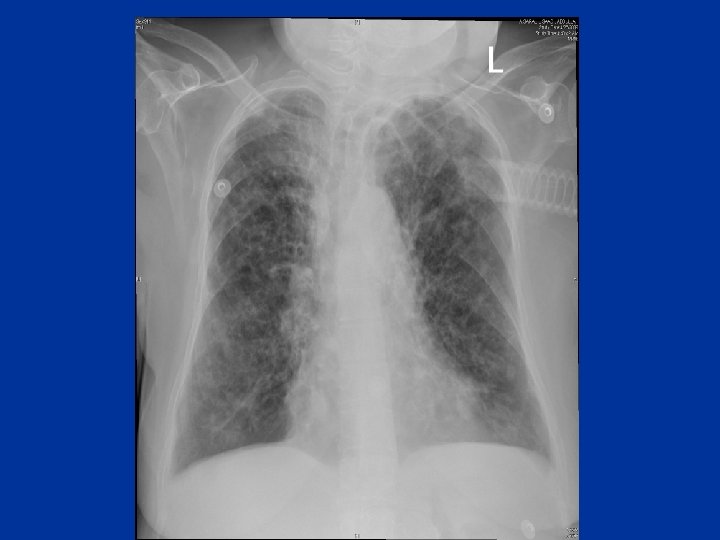

Chronic dyspnea • Major causes: Asthma COPD Bronchiectasis Interstitial lung disease Heart failure or cardiomyopathy

Evaluation • • • History& physical exam CXR PFTS Oximetry Echocardiogram CT-lungs - I. L. D _ Bronchiectasis - Occult emphysema - Chronic thromboembolic dis. • Cardiopulmonary exercise